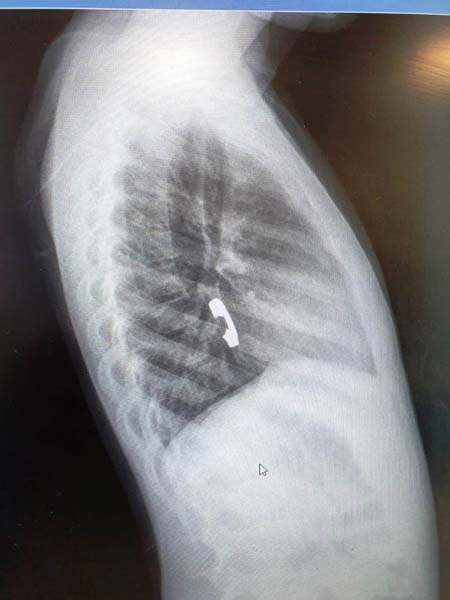

نجح الطاقم الطبي في مستشفى زيف في صفد ، في استخراج خاتم من داخل مريء طفلة ( 6 سنوات ) ، وذلك بعد اجراء عملية لها واخضاعها للتخدير الكلي .

وافاد مستشفى زيف في صفد ان" العملية التي اجريت للطفلة سمحا سويسا من صفد تعتبر بمثابة انقاذ لحياتها وذلك بعد ان ابتلعت الخاتم المرصع بالمجوهرات وشعرت باوجاع في منطقة الصدر، فتم نقلها الى مستشفى زيف في صفد وبعملية حذرة جدا من اجل عدم جرح ألأعضاء الداخلية للطفلة ، تم استخراج الخاتم بنجاح وتسريح الطفلة في اليوم التالي وهي بصحة جيدة " .